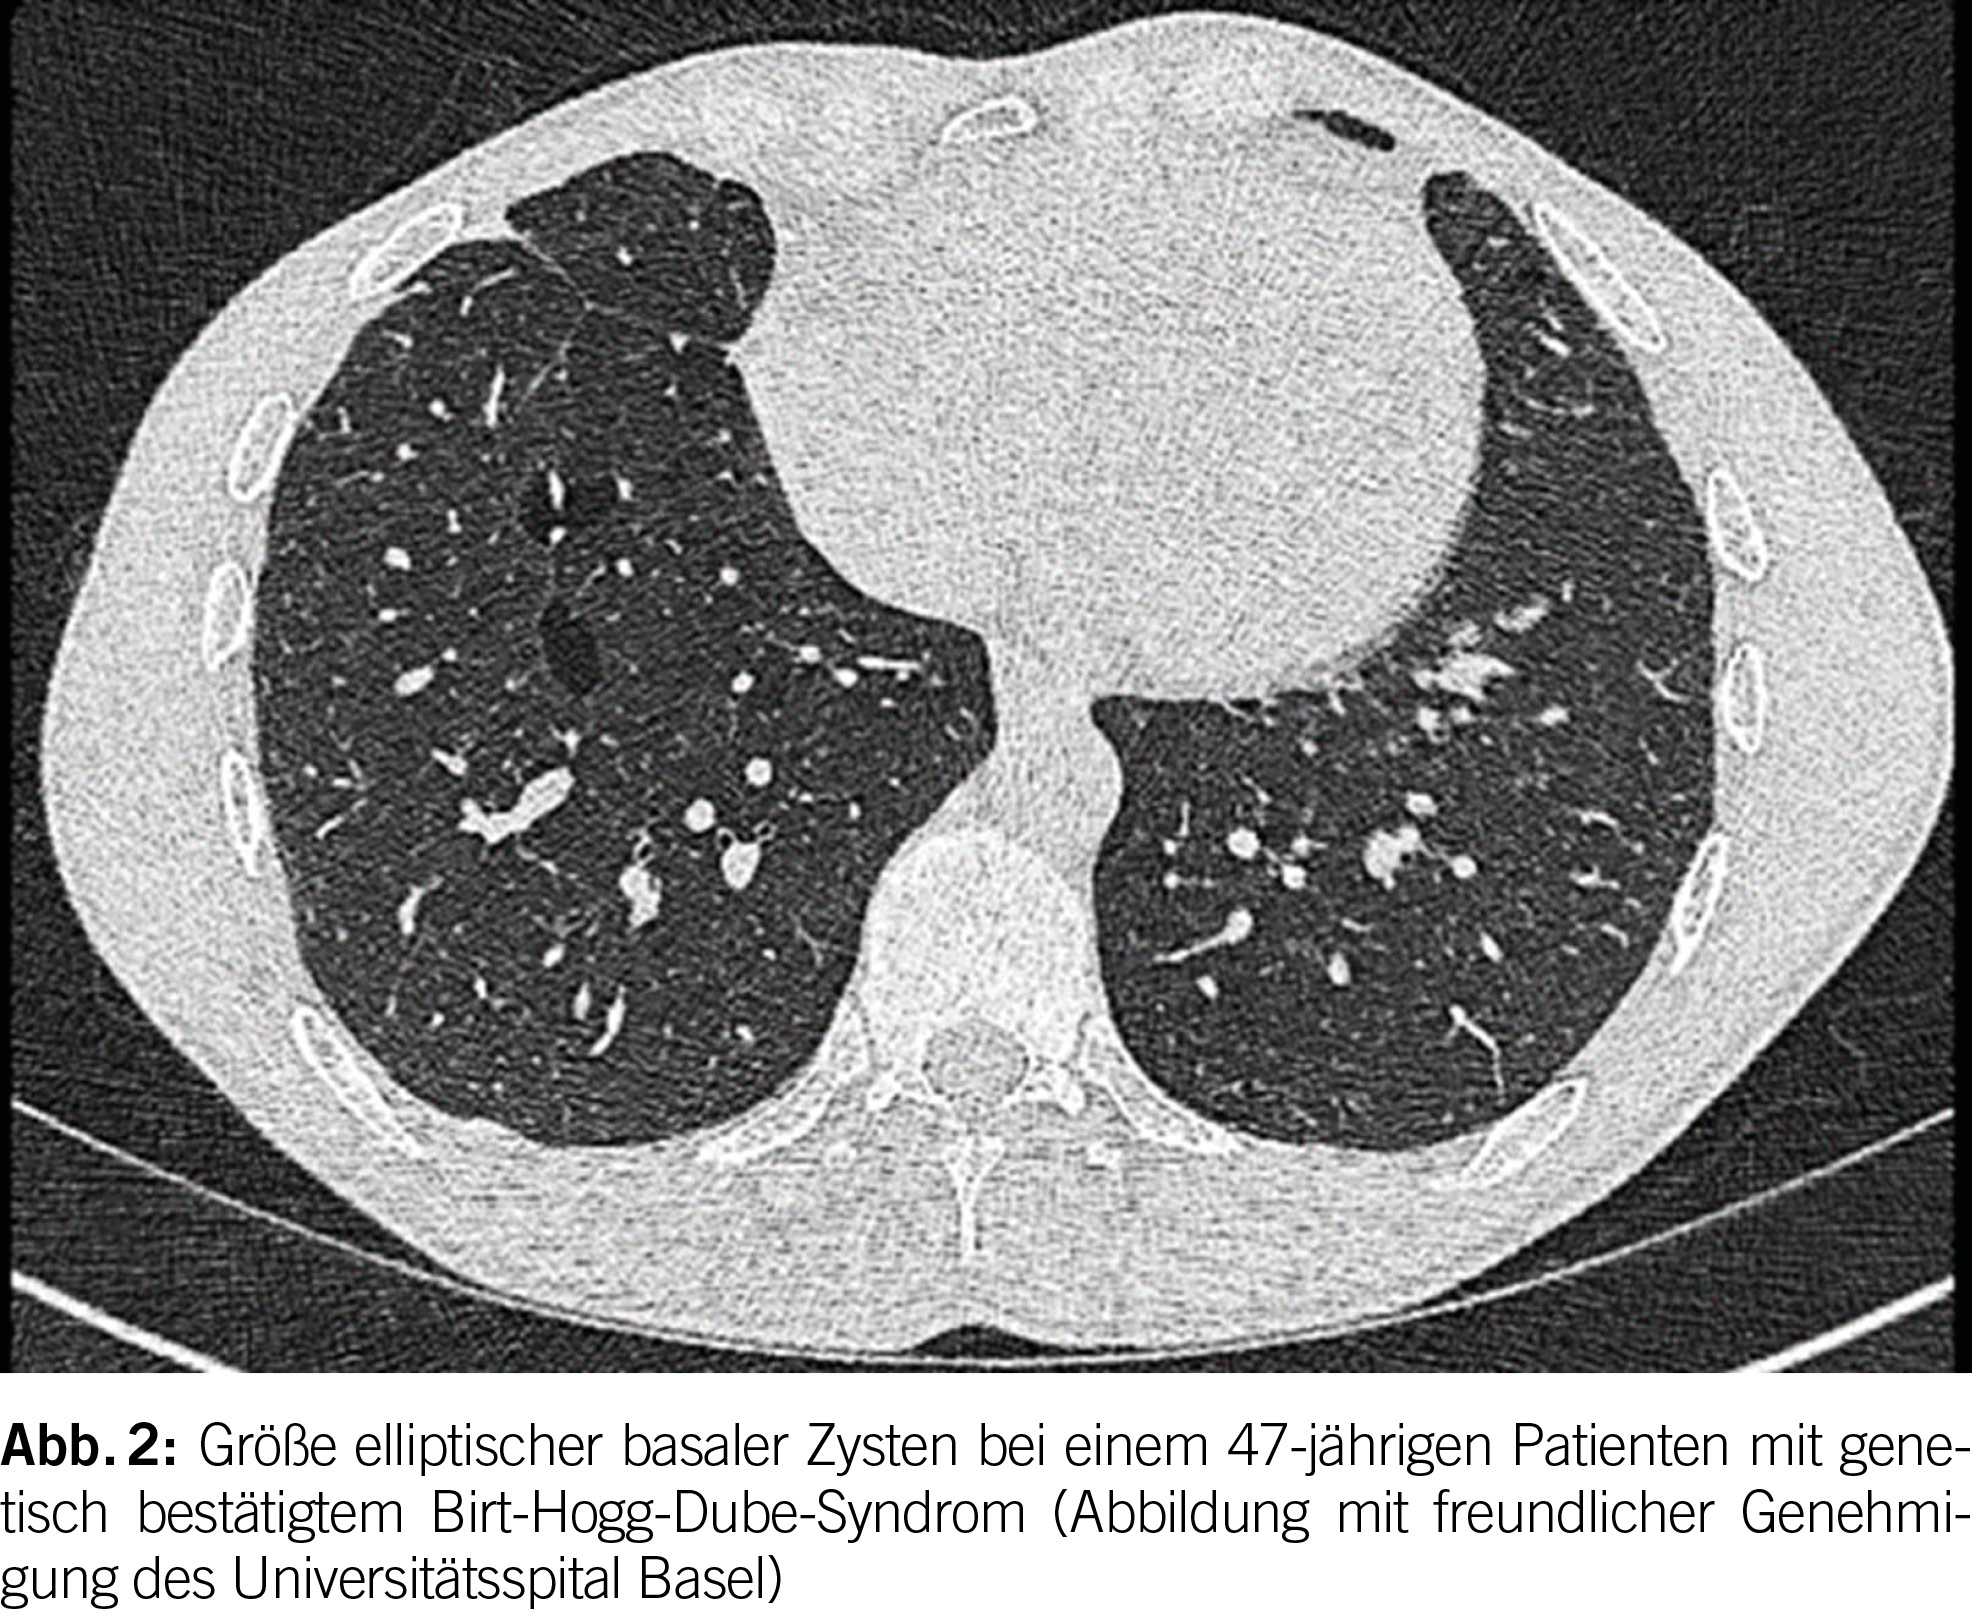

Das Birt-Hogg-Dubé Syndrom (BHD) ist eine seltene autosomal dominante Störung mit einer hohen Penetranz (geschätzt bei 90-95%) (1). Sie entsteht aufgrund von Keimbahnmutationen im Tumorsuppressorgen FLCN, das auf Chromosom 17p11.2 liegt und das Folliculin-Protein codiert. Die phänotypischen Merkmale der Krankheit umfassen eine Triade aus diffusen pulmonalen Zysten, Hautläsionen und renalen Neoplasien unterschiedlicher Histologie. Es betrifft in der Regel junge Erwachsene ohne Geschlechtspräferenz und tritt überwiegend bei Personen im Alter von 20 bis 40 Jahren auf; es kann jedoch in allen Altersgruppen auftreten. Bei BHD werden bei der Mehrheit der Patienten (ungefähr 80%) pulmonale Zysten beobachtet. Diese Zysten weisen im Vergleich zu anderen diffusen zystischen Lungenerkrankungen (DZLE) eine linsenförmige Form, größere Abmessungen und eine basale Dominanz auf (Abbildungen 2 und 3). Eine Studie zu radiologischen Merkmalen, die mit den vier Hauptursachen diffuser Lungenzysten assoziiert sind, zeigte eine deutlich höhere Inzidenz von paramediastinalen Zysten bei Personen mit BHD (2).